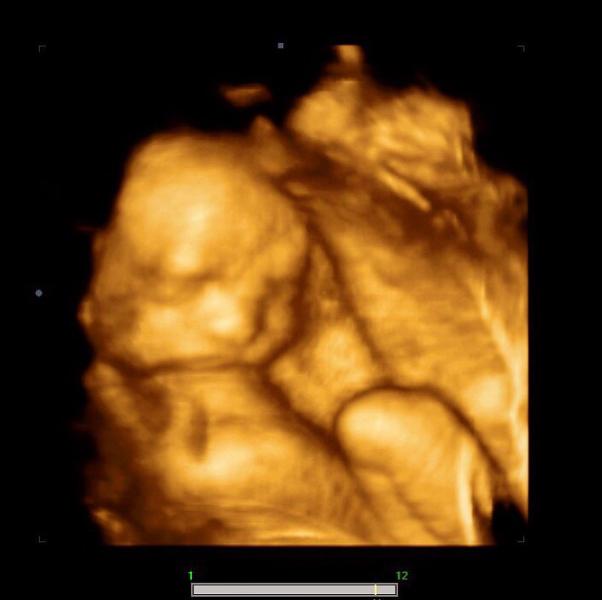

Девочки, сегодня летаю от счастья! 🚀🚀🚀

Я виделась со своим сыночком😍 это просто Мега возможность жить в нынешнее время, потому что повезло полюбоваться таинством, как в тебе растёт крошечный человечек!

Итак, срок по УЗИ #25недель и один день💪🏻

Вес: 870 грамм, стопа 5 см😂

Плацента, воды, шейка матки все в норме👍🏻

В третий раз подтвердили и продемонстрировали нам мужчину ❤️

Лежал, как положено в низ головой, а вообще знаете как лежат на пляже на шезлонге - так это о моем мальчике 😂😂😂 руки за го...